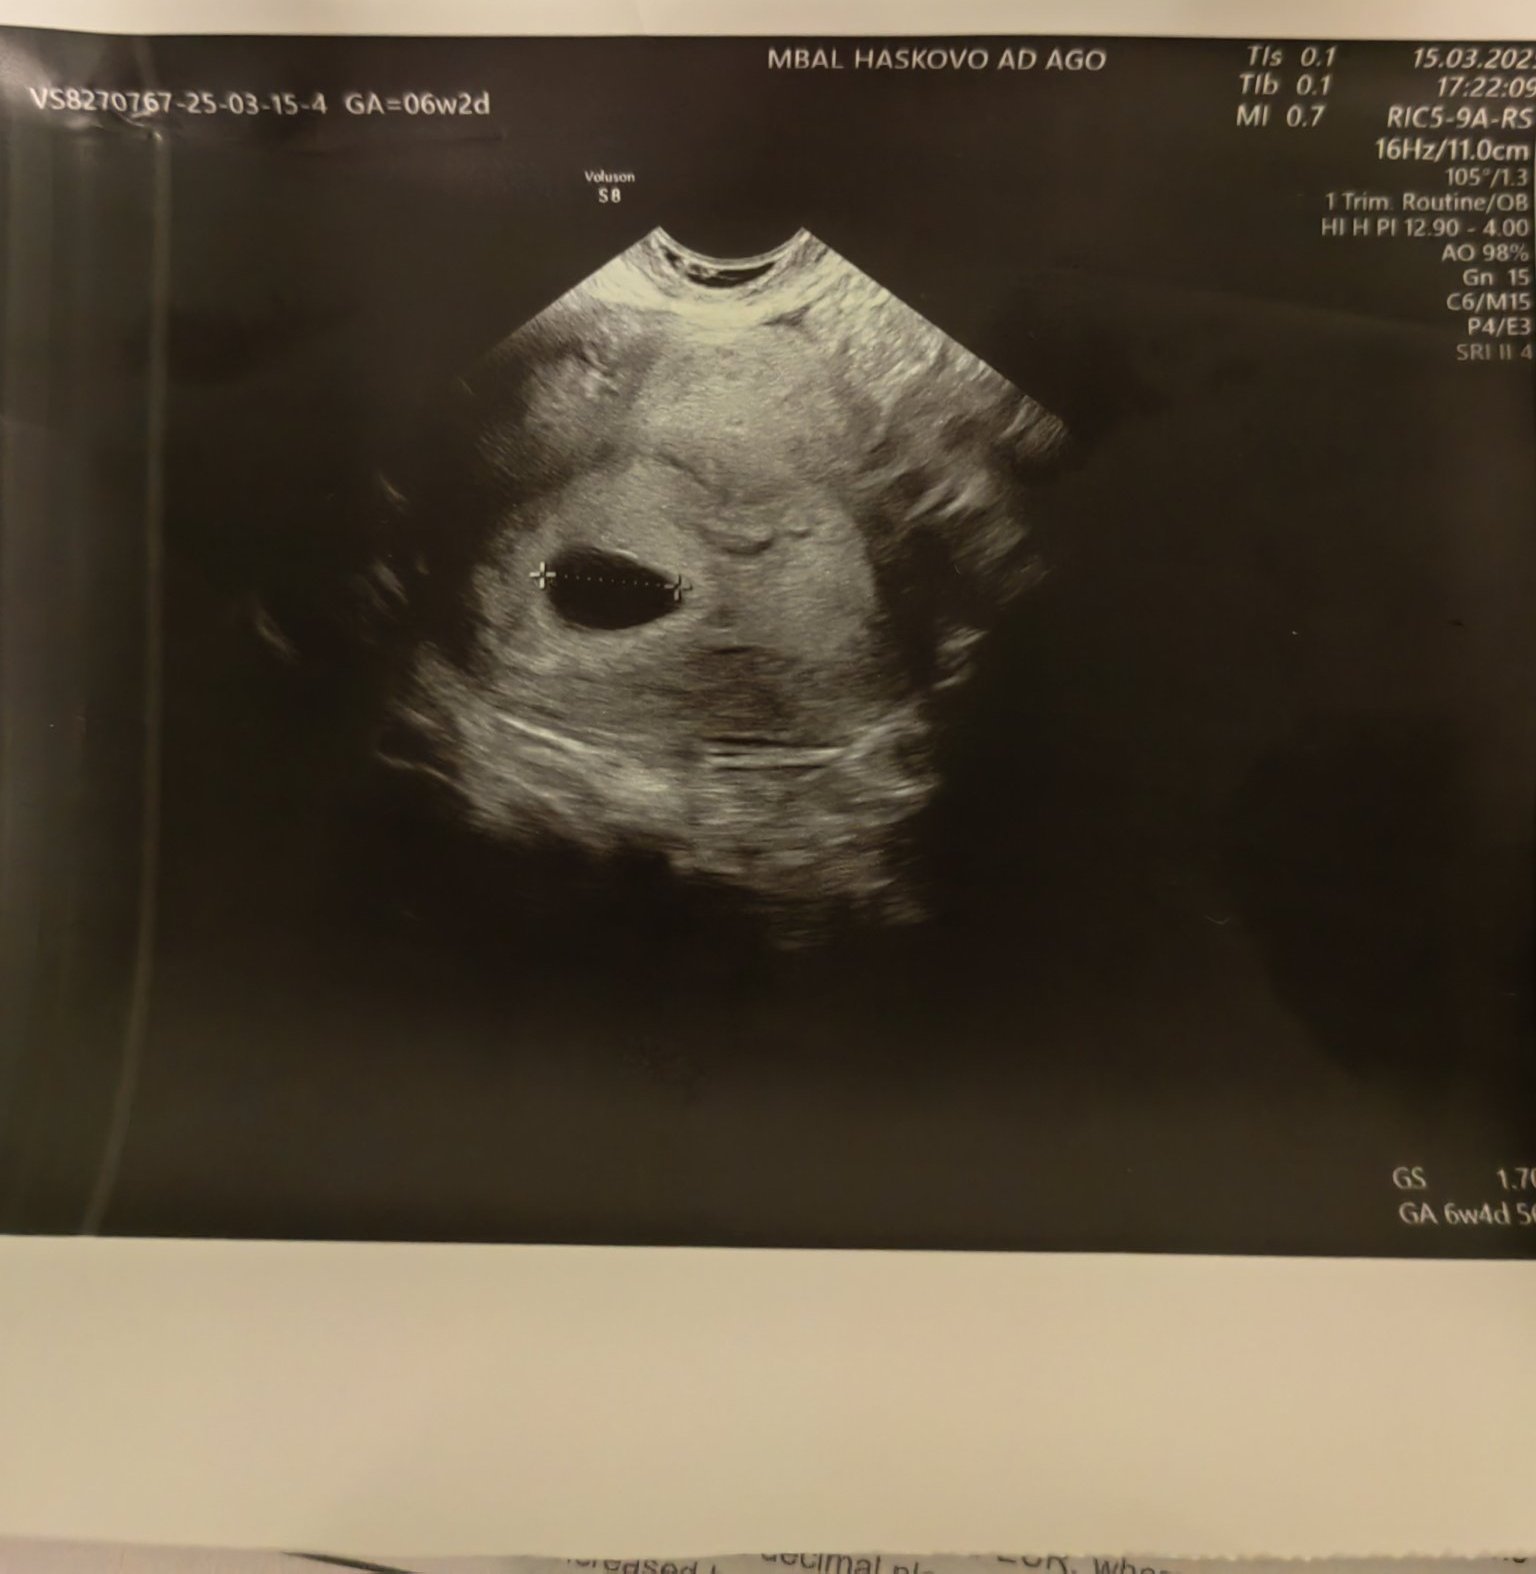

Какво представлява жълтото тяло на ехографската снимка?

Какво представляват черните точки в матката на ехографската снимка?